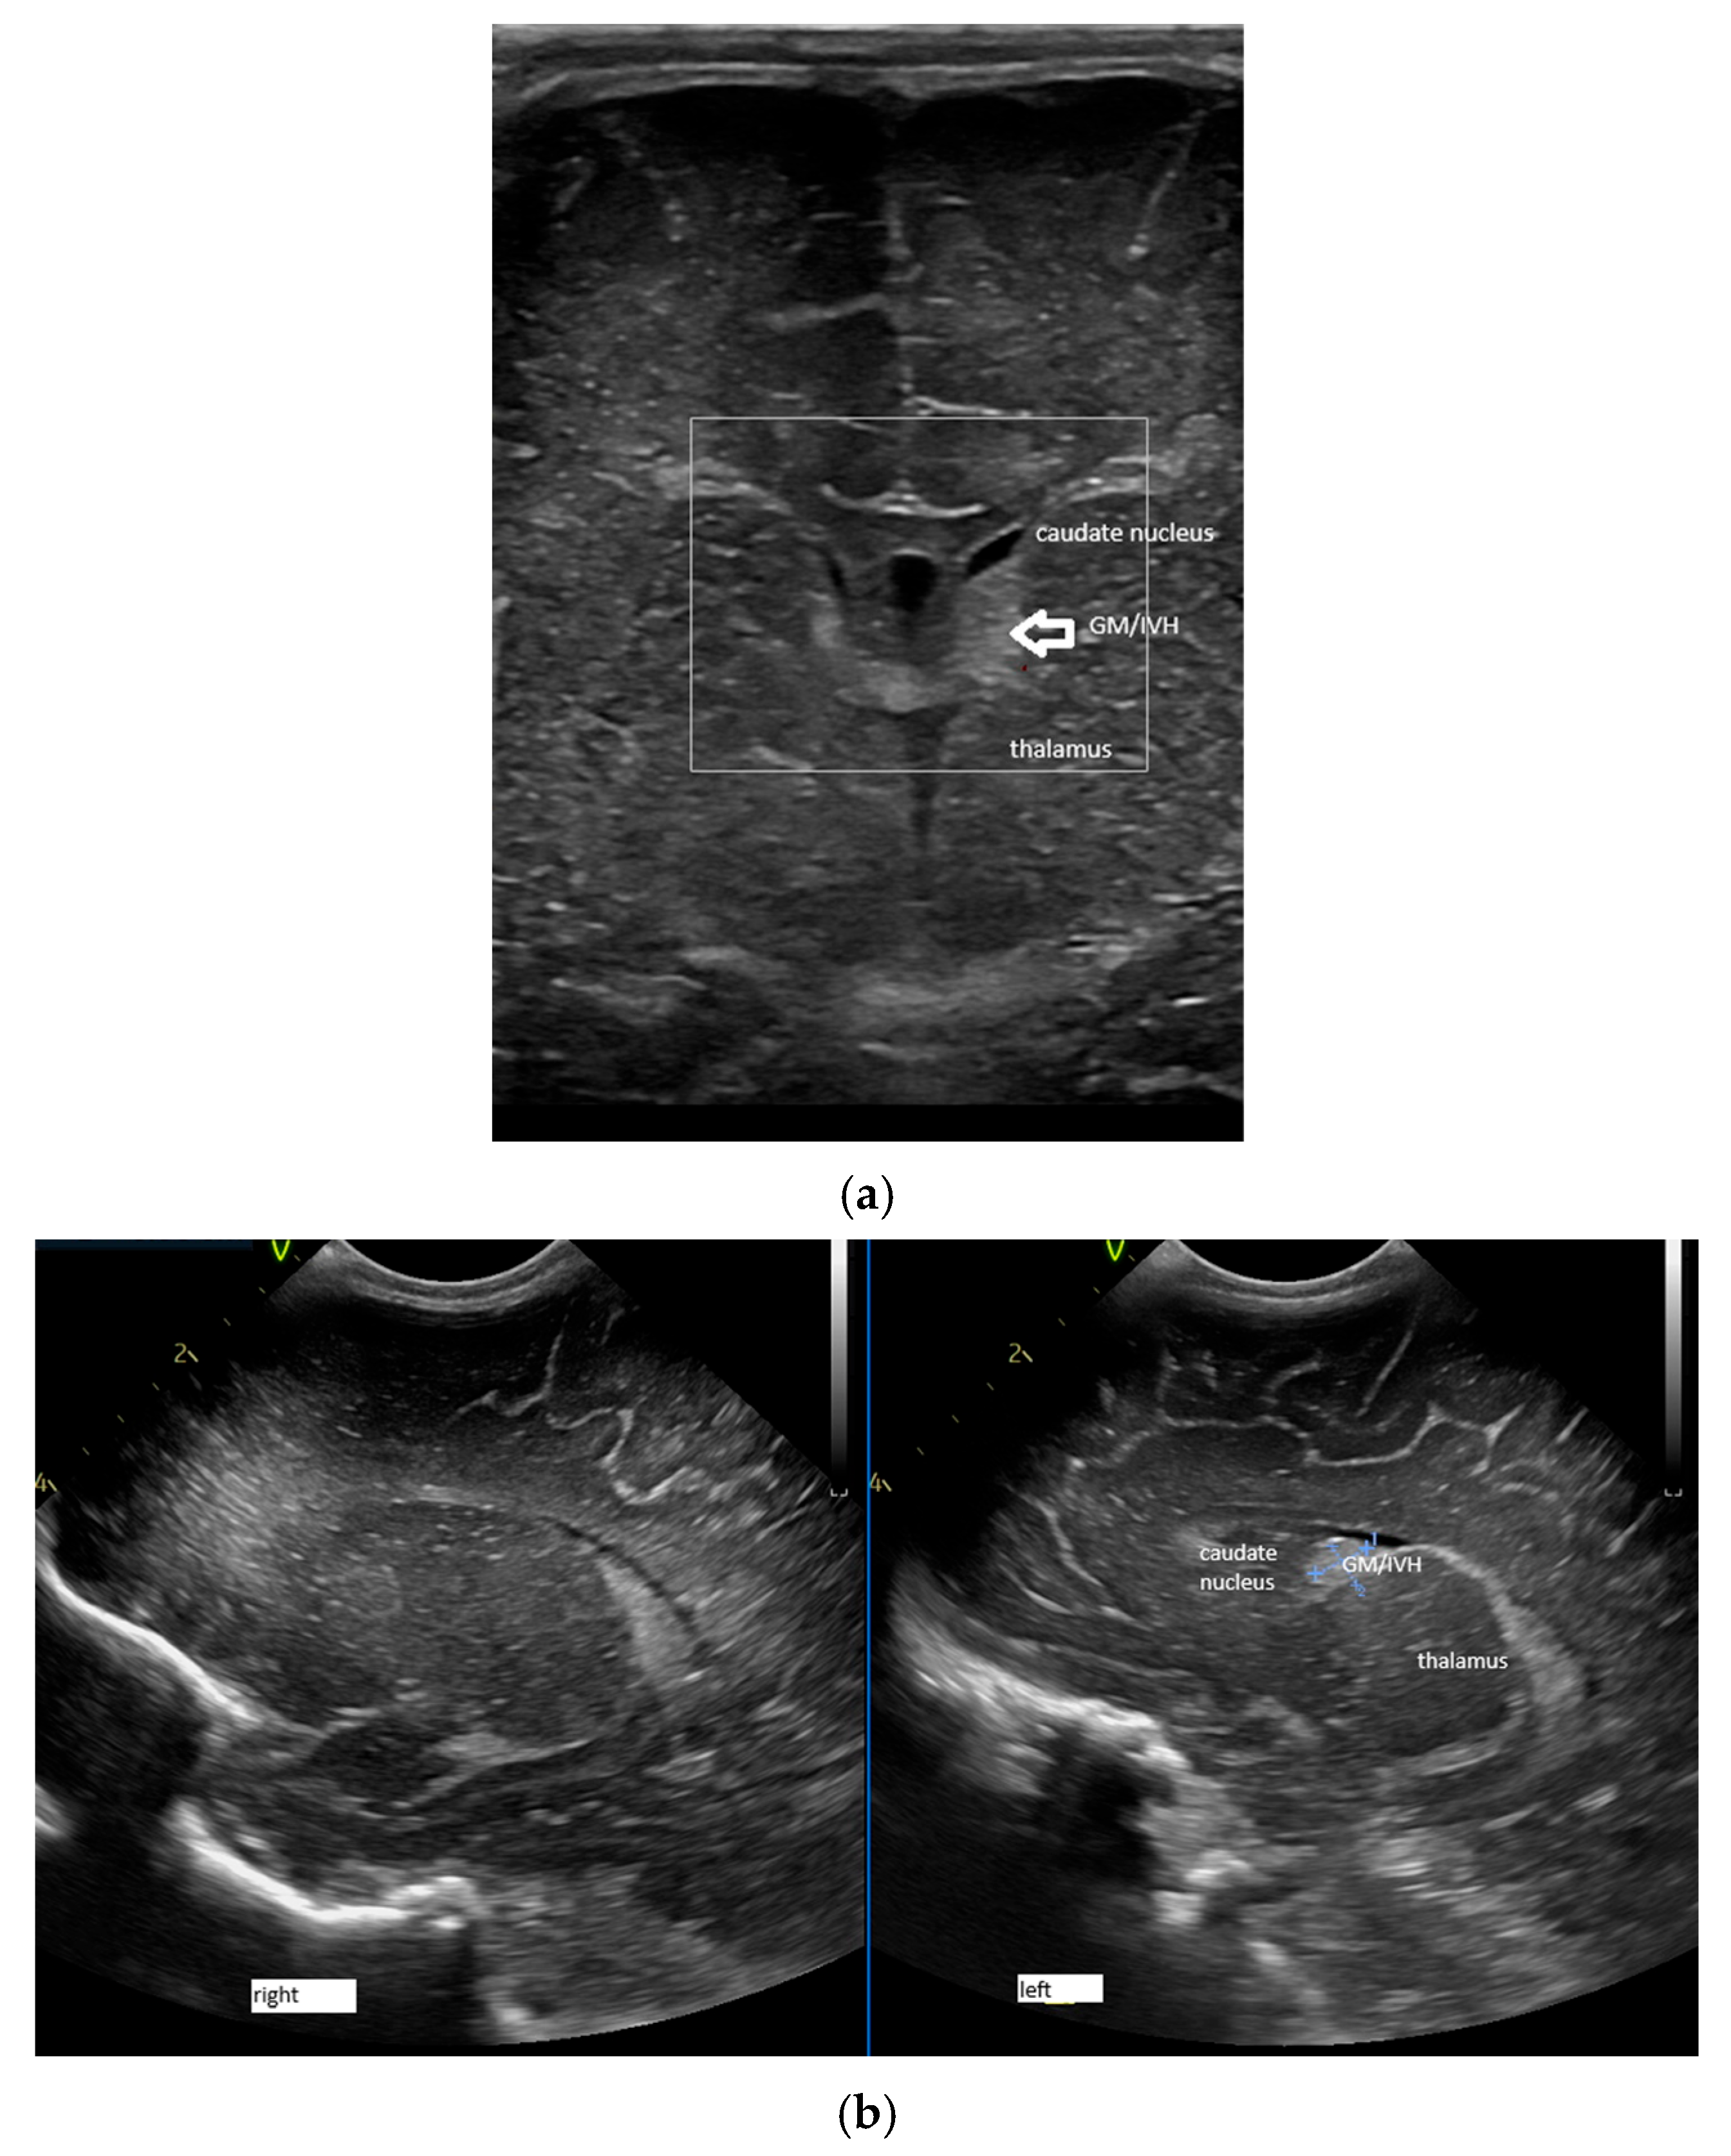

- Confluence posterior to the foramen of Monro, the most frequent variant (Figure 1).